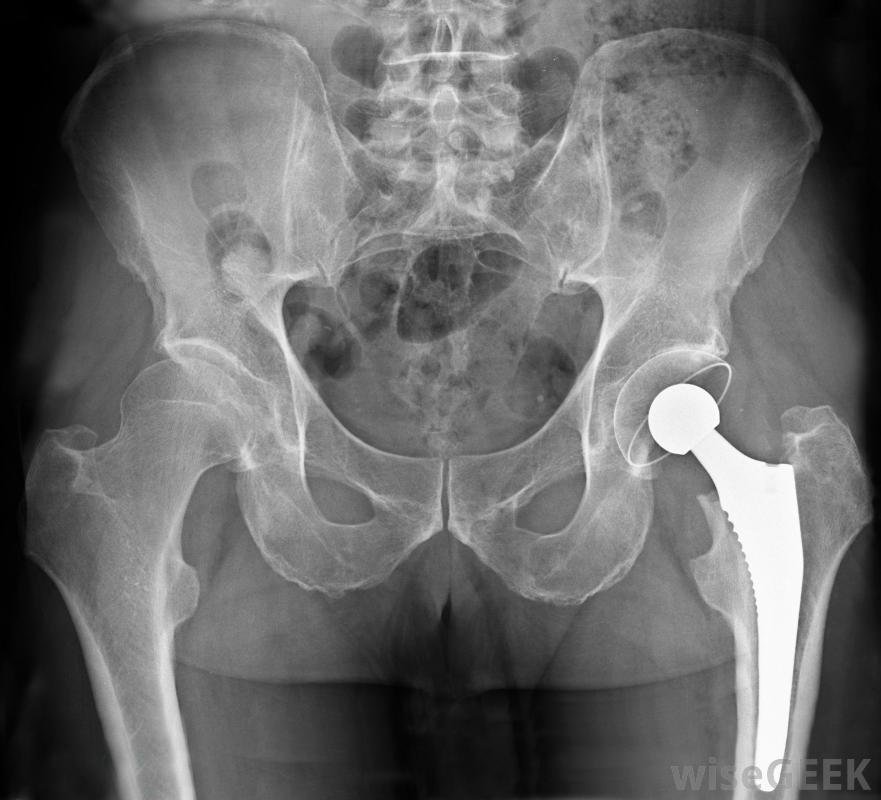

严重的髋关节炎患者可能需要髋关节置换术。诊断通常是在体检和可能的x光检查后作出的。医生将确定活动范围并寻找僵硬和询问疼痛。早期诊断很重要,因为它可以开始治疗并减缓病情的进展。

髋关节炎会导致疼痛、僵硬和执行困难最简单的任务,包括步行。治疗将取决于关节炎的严重程度及其对生活方式的影响。轻微的髋关节炎可以通过营养补充剂、改变生活方式和物理疗法。超重者可建议减肥。在运动或运动中过度使用髋关节的人,可能建议改变活动。在某些情况下,营养补充剂可能会有所帮助。葡萄糖胺和软骨素都是补充剂,被认为有助于减缓关节损伤,并有可能促进新的软骨发育在你开始服用补充剂之前,最好咨询一下你的医生药物治疗也有助于减轻关节炎引起的疼痛。消炎药,如布洛芬,可能会有帮助。如果非处方药没有帮助,更强烈的疼痛和抗炎药可能需要医生开如果其他治疗方法不起作用,且症状严重,则可能需要进行髋关节置换手术。髋关节置换手术分为部分置换术和完全置换术两种。如果髋关节损伤严重,则可能需要进行全髋关节置换术疼痛是髋关节炎的主要症状。